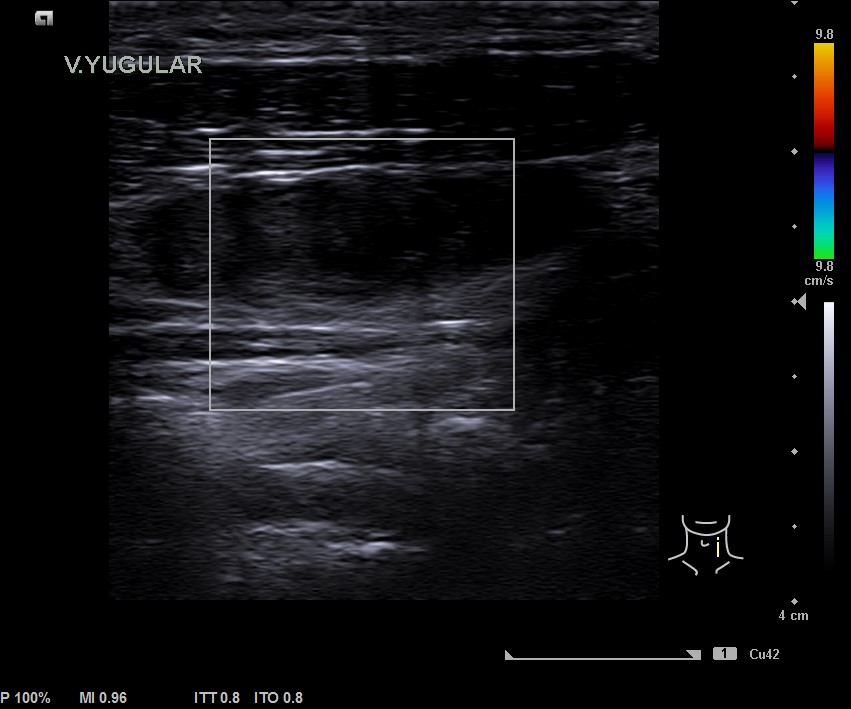

En la ecografía tiroidea se observa en LTI nódulo de 10 mm de bordes mal definidos, lobulado, mayormente sólido, más alto que ancho, isoecogénico, halo periférico hipoecoico, vascularización difusa, que sugiere TIRADS 5. Ausencia de flujo en Vena yugular interna izquierda, ensanchada, que sugiere trombosis yugular aguda o subaguda y junto a ella, posible conglomerado adenopático.